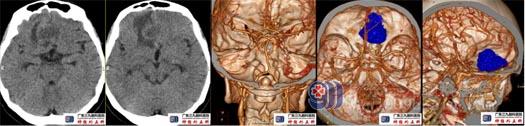

术前头颅CT、CTA示右侧额叶底部镰旁占位性病变,其实性部分示稍多细小血管影,邻近双侧大脑前动脉局部受压左偏。